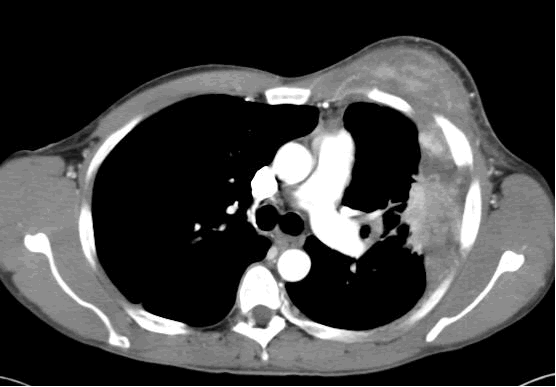

PA and lateral chest film revealed patchy consolidation of the left lung with a large pleural-based mass, left apical pleural thickening, and right upper lobe scarring (Figure 1). Helical CT scan of the chest, abdomen, and pelvis with contrast demonstrates a large, 10.8 x 4.1 cm left pleural-based mass extending into the chest wall and left breast (Figure 2). There was periosteal thickening and irregularity of adjacent ribs. Multiple enlarged mediastinal, left hilar, and supraclavicular nodes were noted, the largest 1.5 x 2.6 cm in the AP window or station five region. There was patchy consolidation of the left and right upper lobes. An MRI of the thorax with contrast was obtained and confirmed the presence of left supraclavicular adenopathy and an enhancing mass with extension into the chest wall involving the ribs, infiltration of the pectoralis muscle, and extension into the left lung parenchyma. The main differential diagnoses at this time were neoplasm (sarcoma, advanced lung cancer, mesothelioma, lymphoma, osteosarcoma).